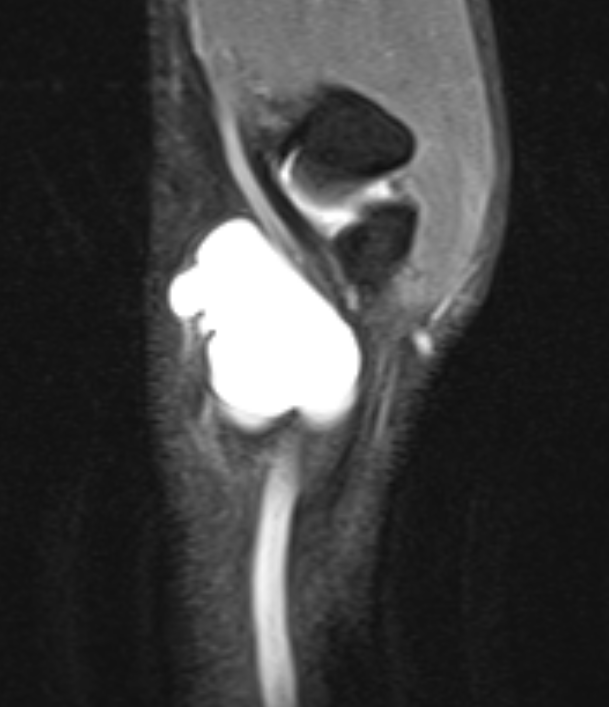

Volar ganglion